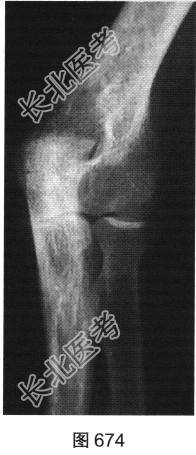

患者女性,62岁,右侧肘关节肿胀、疼痛1年余。肘关节正侧位X线片及CT检查见图673~图676。

- 多项选择题1.对该患者影像征象描述正确的是( )

A、关节腔积液

B、尺骨关节面囊状骨质破坏

C、肘关节面明显骨质增生硬化

D、肘关节软组织肿胀

E、尺骨近段骨膜反应

F、肘关节间隙变窄

G、骨质疏松